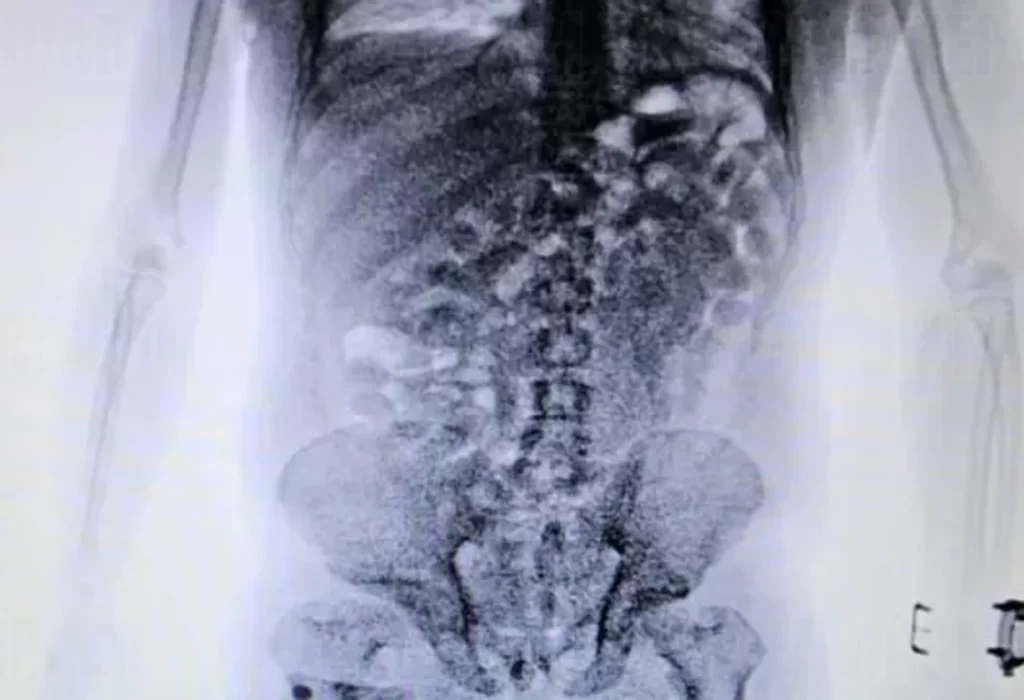

En el Aeropuerto Internacional de Ezeiza, agentes especializados de la Dirección General de Aduanas detectaron a un ciudadano brasileño que levantó sospechas debido a su elevado nivel de nerviosismo mientras realizaba el check-in para un vuelo de Air France con destino a Málaga vía París. Aunque la inspección inicial de su equipaje no reveló irregularidades, el persistente comportamiento extraño llevó a una inspección más detallada mediante un body scan.

Las imágenes confirmaron las sospechas al revelar la presencia de 84 cápsulas de cocaína en su cuerpo. La droga, con un valor estimado de USD 51,000 en el destino, fue confiscada, y el individuo quedó detenido, enfrentando cargos por contrabando de estupefacientes. Este operativo destaca la importancia de las tecnologías avanzadas en la detección de métodos de ocultamiento de drogas y la efectividad de los protocolos de seguridad implementados por la Aduana.